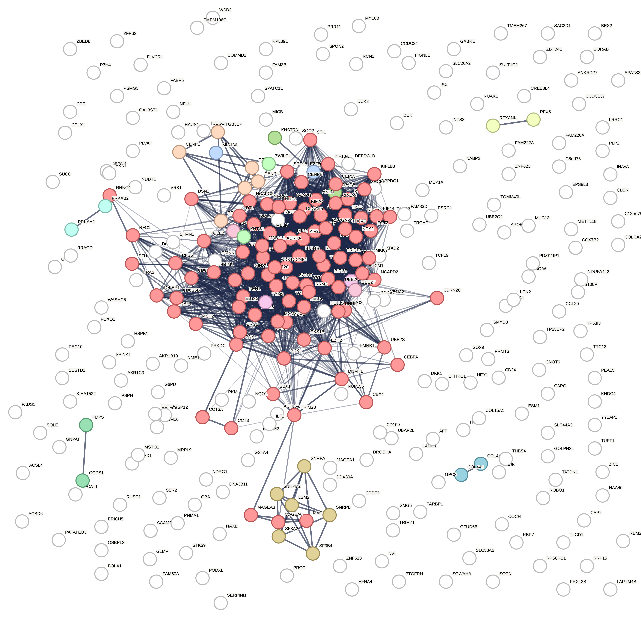

The intersection of DEGs from the TCGA and GEO databases revealed 324 co- upregulated genes (Figure 3A) and 321 co-downregulated genes (Figure 3B). These common upregulated and downregulated genes were further analyzed for their interaction networks using the STRING database, revealing widespread gene interactions. The DBSCAN clustering algorithm identified 12 clusters for upregulated genes and 24 clusters for downregulated genes. The most central cluster in the upregulated genes was designated as cluster 1, serving as a hub gene, while the most central clusters in the downregulated genes were clusters 1 and 2, which were also considered hub genes. Figures 4 and 5 illustrate the clustering of interaction proteins and their network distributions. A total of 94 hub genes showed increased expression, while 37 showed decreased expression.